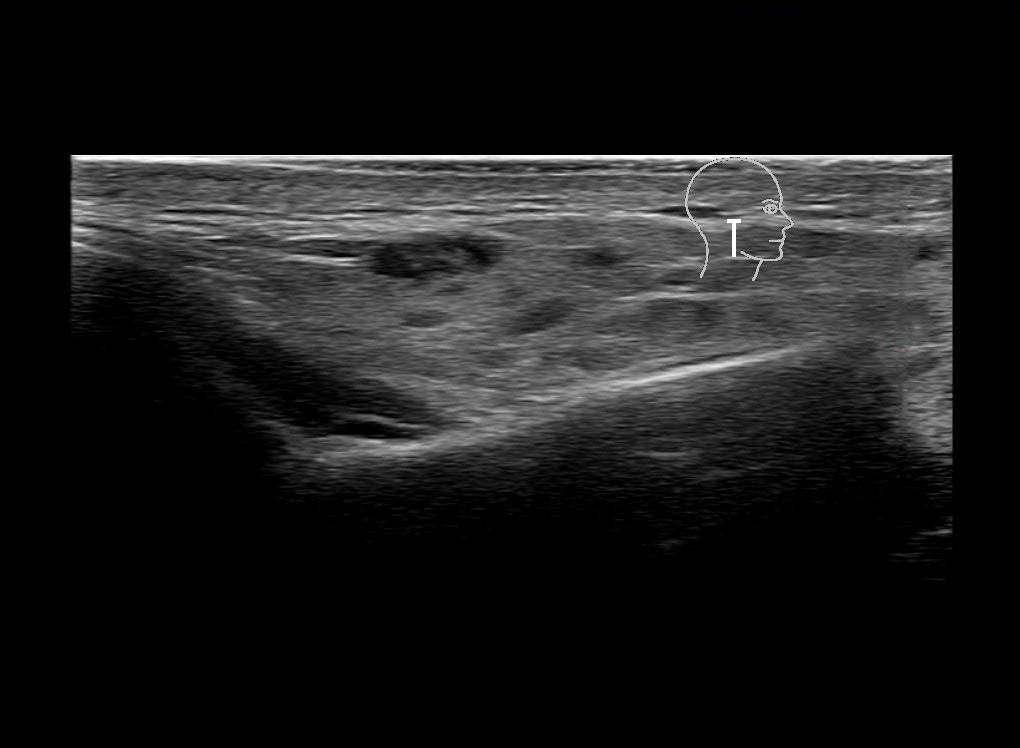

Study the first image to recognize the different layers. If you are sure about the layers, swipe to the second image to view the answer (if applicable).

Hover over an image to view the secondary image or click on the image title for more information.